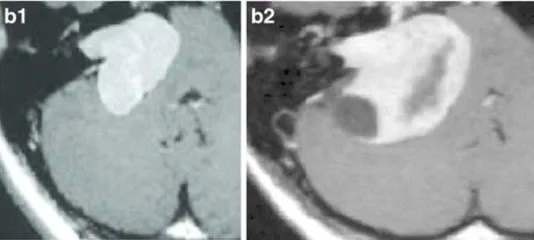

下图显示了放射治疗失败的其他病例,与这些患者相比,这些患者表现出更快的肿瘤再生长和更严重的临床症状(图3a–c)。由于脑干受压增加,这些病例都需要在伽玛刀治疗后3年内进行显微手术切除。图3d–f展示了立体定向放射治疗(SRT)之后的一些放射学变化。

a-38岁女性。a-1增强后轴向MRI显示右侧中等大小的肿瘤(伽马刀治疗前)。a-2增强后轴向MRI显示肿瘤生长压迫脑干和小脑(伽马刀治疗后2年)。

b-22岁女性。b-1增强后轴向MRI显示右侧中等大小的肿瘤(伽马刀治疗前)。b-2增强后轴向MRI显示肿瘤进一步生长压迫脑干和小脑(伽马刀治疗后3年)。肿瘤缺乏中央强化,可见小囊肿形成。

c-28岁女性。c-1增强后轴向MRI显示左侧中等大小的肿瘤,均匀强化(伽马刀治疗前)。c-2增强后的轴位MRI显示肌内和肌外部分的生长(伽马刀治疗后2年)。